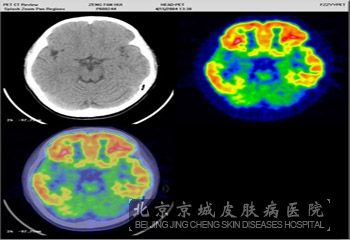

神经纤维瘤的颅内肿瘤症状有哪些呢?神经纤维瘤是常见的遗传性疾病,具有此病的患者一般会有明显的神经症状表现,但是这些症状主要表现在神经干上,由于中枢或周围神经肿瘤压迫造成的,其中有颅内肿瘤、椎管内肿瘤等。那么神经纤维瘤的颅内肿瘤症状有哪些呢?

北京京城皮肤医院介绍说:神经纤维瘤的颅内肿瘤症状主要发生的就是听神经瘤,一般常合并脑膜脊膜瘤、多发性脑膜瘤、神经胶质瘤、脑膜膨出及脑积水、脊神经后根神经鞘瘤等,视神经、叁叉神经、后组脑神经等都可发生病变,有些甚至会有记忆障碍及痫性发作等症状。